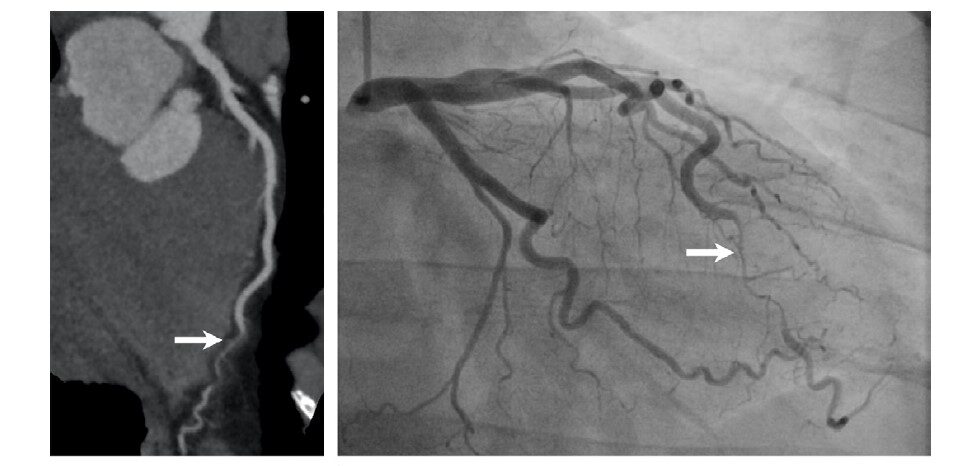

35歲女性出現劇烈胸痛,CCTA(左圖)及血管攝影檢查(右圖)顯示左前降枝冠狀動脈遠端呈現突然變細、平滑且瀰漫性之嚴重狹窄(箭頭)。Radiology: Cardiothoracic Imaging 2020; 2(6):e200364